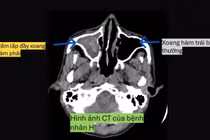

Kết quả chụp hình ảnh học xác định bệnh nhân bị viêm đa xoang nghi do nấm xâm lấn, đã có biến chứng lan sang ổ mắt và thần kinh thị. Đây là tình trạng cực kỳ nguy hiểm, có thể dẫn đến mù lòa, thậm chí đe dọa tính mạng nếu không được xử trí kịp thời.

viem-xoang-nam.png